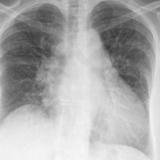

APE 6

+ IABP

Date: 01/13/2008

Views: 3390